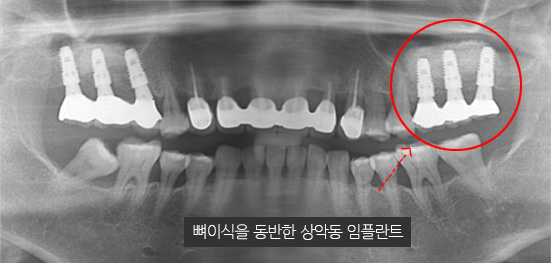

잇몸 뼈가 녹아내려 임플란트 12개 진단을 받고 내원한 환자, 고운미소에서 치주치료를 시행한 결과 전치부 잇몸이 개선되어 발치 하지 않고

크라운으로 수복하였고, 어금니는 상악동거상술 후 6개의 임플란트를 식립하였습니다.

잇몸 염증으로 치조골 손실이 많은 상태

잇몸 건강이 회복된 앞니는 크라운으로 수복